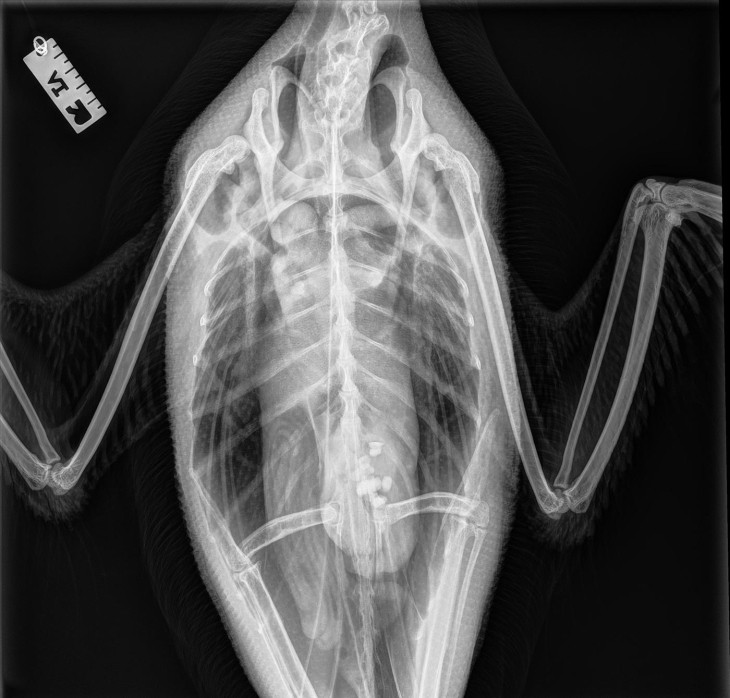

Next, the team brought the loons to VCA Capital Area Veterinary Emergency and Specialty (CAVES) in Concord, New Hampshire, where technicians took radiographs (x-rays) to rule out the presence of internal injuries or ingested fishing tackle. Although the birds were a bit thin after their ordeal, the x-rays did not reveal any cause for concern. (The foreign objects visible in this loon’s lower body are stones, ingested and stored in the gizzard to aid in digestion of hard food items.) The loons were then transferred to Wings of the Dawn Wildlife Rehabilitation Center in Henniker, where rehabilitator Maria Colby treated the lead-poisoned bird and kept all 10 for feeding and observation. In the day they spent at Wings of the Dawn, they collectively ate nearly 30 pounds of fish!

Loon radiograph

Photo by VCA CAVES